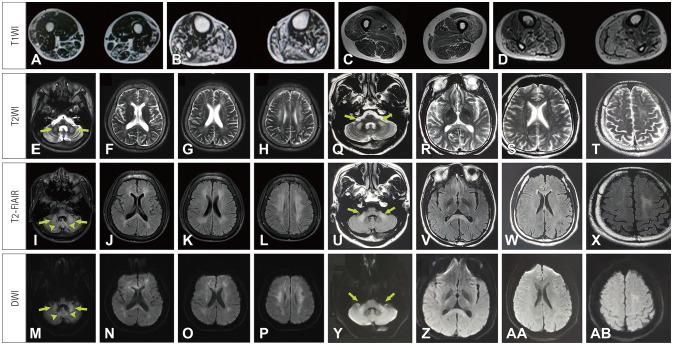

Our two OPDM3 patients and most patients reported in the literature developed the typical clinical characteristics of NIID, including leukoencephalopathy, peripheral neuropathy, cognitive deterioration, pigmentary retinopathy, ataxia, tremor, acute encephalitis-like episodes, pigmentary retinopathy, miosis, and sensorineural hearing loss. In addition to typical imaging findings of NIID, our two patients exhibited diffusion weighted imaging (DWI) hyperintensities in the middle cerebellar peduncles, which have not been described previously. Muscle biopsies revealed rimmed vacuoles and p62-positive intranuclear inclusions in the myofibers in both patients. The skin biopsy performed in one patient detected typical eosinophilic intranuclear inclusions. Genetic analysis identified CGG repeat expansion in as the causative mutation in the two patients.

我们的两名OPDM3患者以及文献中报道的大多数患者都出现了NIID的典型临床特征,包括白质脑病、周围神经病变、认知衰退、色素性视网膜病变、共济失调、震颤、急性脑炎样发作、色素性视网膜病变、瞳孔缩小和感音神经性听力损失。除了NIID的典型影像学表现外,我们的两名患者在小脑中脚出现了扩散加权成像(DWI)高信号,这在以前尚未有过描述。肌肉活检显示两名患者的肌纤维中均有边缘空泡和p62阳性核内包涵体。对一名患者进行的皮肤活检检测到典型嗜酸性核内包涵体。基因分析确定中CGG重复扩增是这两名患者的致病突变。